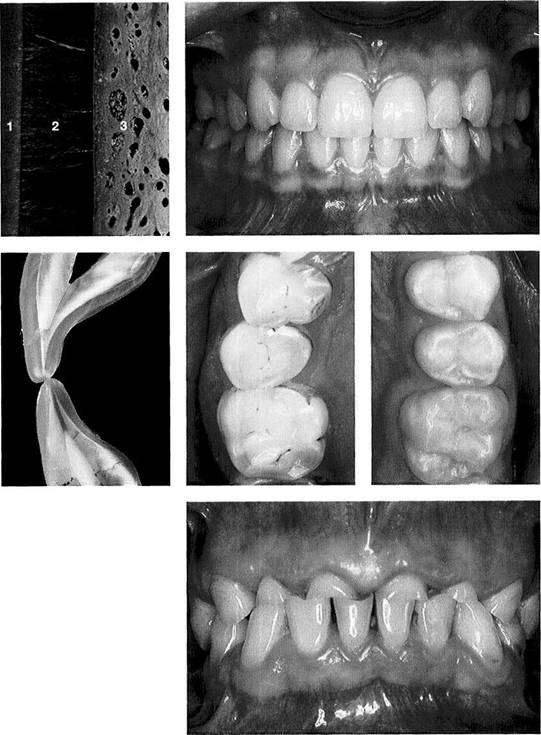

Anatomy of the Masticatory System

Glenoid Fossa and Articular Protuberance

The temporal portion of the joint can be divided into four functional parts from posterior to anterior: postglenoidal process, glenoid fossa, articular protuberance, and apex of the eminence. The inclination of the protuberance to the occlusal plane varies with age and function (Kazanjian 1940), but is 90% determined at the age of 10 years (Nickel et al. 1988). Three fissures can be found at the transition to the tympanic plate of the temporal bone: the squamotym-panic, petrotympanic, and petrosquamous fissures (Fig. 28). In patients with disk displacement, these fissures are fre-

quently ossified (Bumann et al. 1991). Under physiological conditions the only parts of the temporal portion of the joint that are covered with secondary cartilage are the protuberance and the eminence (Fig. 31). Secondary cartilage is formed only when there is functional loading. Before the fourth postnatal year stimulation of the cells of the perio-seum leads to the formation of secondary cartilage (Hall 1979, Thorogood 1979, Nickel et al. 1997). With no persisting functional load the chondrocytes of the condyle would differentiate into osteoblasts (Kantomaa and Hall 1991).

Inclination

of the articular

protuberance to the occlusal

plane

This graph (adapted from that of Nickel et al. 1988) indicates the inclination of the posterior slope of the eminence (articular protuberance) in relation to the occlusal plane. Accordingly, at the age of 3 years the eminence has reached 50% of its final shape (Nickel et al. 1997). Between the tenth and twentieth year there is a difference of only 5°. The study material originates from the osteological collection of Hamman-Todd and Johns Hopkins, Cleveland Museum of Natural History.

Joint

region of the temporal

bone

Inferior view of the temporal portion of a defleshed temporomandibular joint. Near the upper border of the picture is the articular eminence (1) and at the far left is the external auditory meatus (2). In the posterior portion of the fossa the squamotympanic fissure (3) is found laterally, and the petrosquamous (4) and petrotympanic (5) fissures are found medially. Both the superior stratum of the bilaminar zone and the posterior portion of the joint capsule, and sometimes also the fascia of the parotid gland can insert into these fissures.

Ossification

of the fissures

and disk displacement

Inferior view of a temporal bone with partially ossified fissures. The lateral half of the squamotympanic fissure is completely ossified (arrows). The superior stratum of the bilaminar zone can now insert only into the periosteum in this region. It has been shown that these fissures are ossified in more than 95% of patients with disk displacement, whereas in joints without disk displacement normal fissure formation prevails (Bumann et al. 1991).

Inferior view of the temporal cartilaginous joint surface and capsule attachment

Caudal view of the left temporomandibular joint of a newborn. The bony portions have been separated from the periosteum up to the circular insertion of the capsule and bilaminar zone. Part of the zygomatic arch (1) can be seen near the right border of the photograph. The fibrocartilaginous articular surfaces over the articular protuberance are thickened medially and laterally (arrows). When covered with synovial fluid they allow movements with virtually no friction (Smith 1982).

Sagittal

histological section

showing buildup of the temporal

joint components

The temporal portion of the joint can be divided into four functional components: 1 postglenoidal process, 2 glenoid fossa, 3 articular protuberance, and 4 apex of the eminence. As a rule, no cartilage can be identified within the fossa. The average thickness of the fibrous cartilage over the protuberance and the eminence is between 0.07 and 0.5 mm (Hansson et al. 1977). As this photograph shows, there can be considerable variation in thickness within the same individual.

Function

and structural

adaptation of the articular

eminence

A summary of the basic anatomical changes in the temporal joint tissues. Increased functional loading will cause hypertrophy through secondary cartilage formation and bone deposition (progressive adaptation). Persistent nonphysiological loading (massive influences) leads to deforming or degenerative changes. This regressive adaptation is accompanied by more or less noticeable rubbing sounds, sometimes in combination with pain.